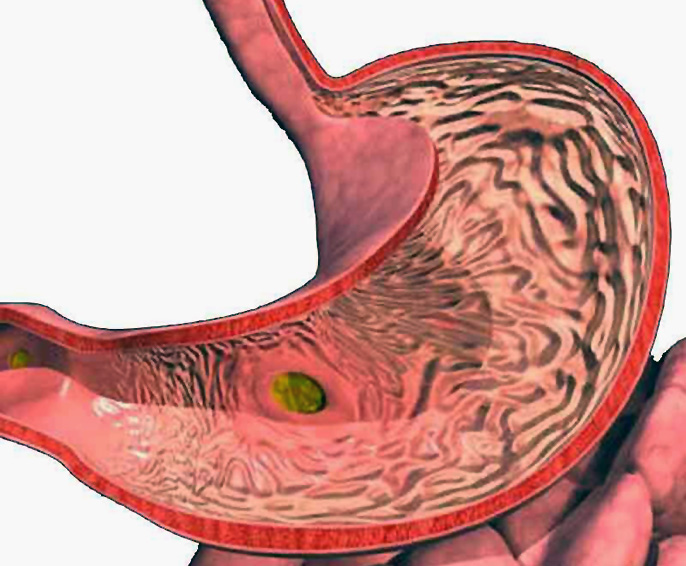

Информация и фотографии о хроническом гастрите и дуодените